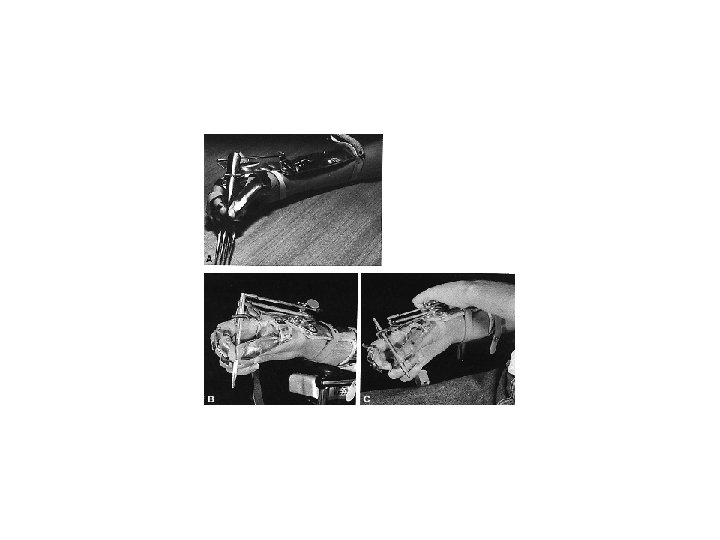

Terapi Prinsip • Konservative – bed rest 6 mg – 6 mg brace – 6 mg rehabiltation • Operatif – Screw and Plate dll • Reposisi • Immobilisasi – Eksternal – Internal